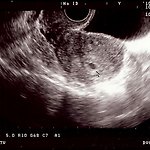

5주 초음파사진~ 5주라고 하네요~ ^^ 2주후 다시 검사 받으러 갑니다... 2주후에는 심장소리도 들을수있다고 해요.. :) 사랑해~ 스카이 IM-A630K [이자르폰] IZAR구혜선폰특가행사!! 가입비 면제 (24000원) / 유심비 면제 / 할부채권료 면제 (보상기변 제외) 가죽케이스/젤리케이스/광학필름/통합젠더/24핀충전기/차량용통합충전기/정전식터치펜 다 공짜!!